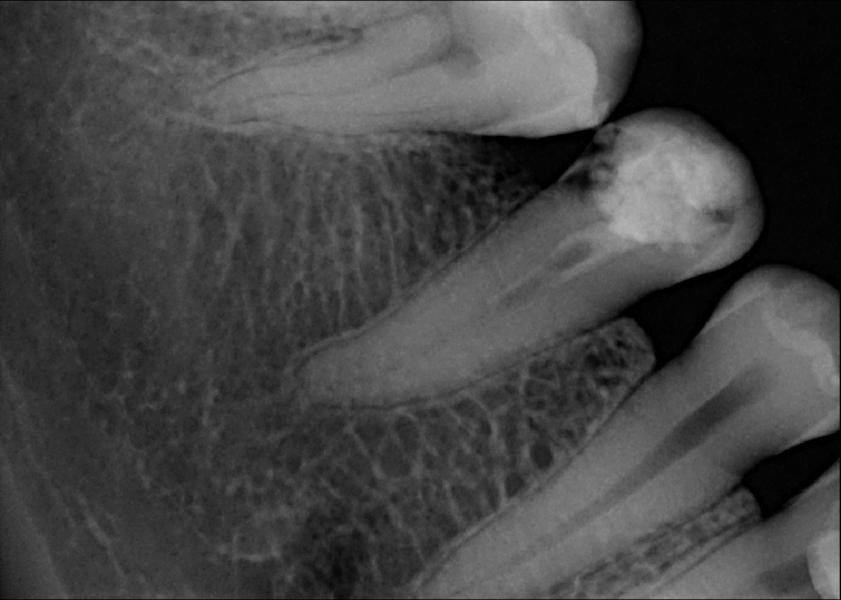

Стоматологи, есть гранулема? Или воспаление в кости? 🙏

Явной гранулёмы не видно,

🔹 Но есть подозрение на воспаление в апикальной области, особенно с учётом разрушенной коронковой части.

🔹 Лучше уточнить у стоматолога: возможно, потребуется эндодонтическое лечение (если зуб подлежит восстановлению) или удаление.

Да видно, где затемнение